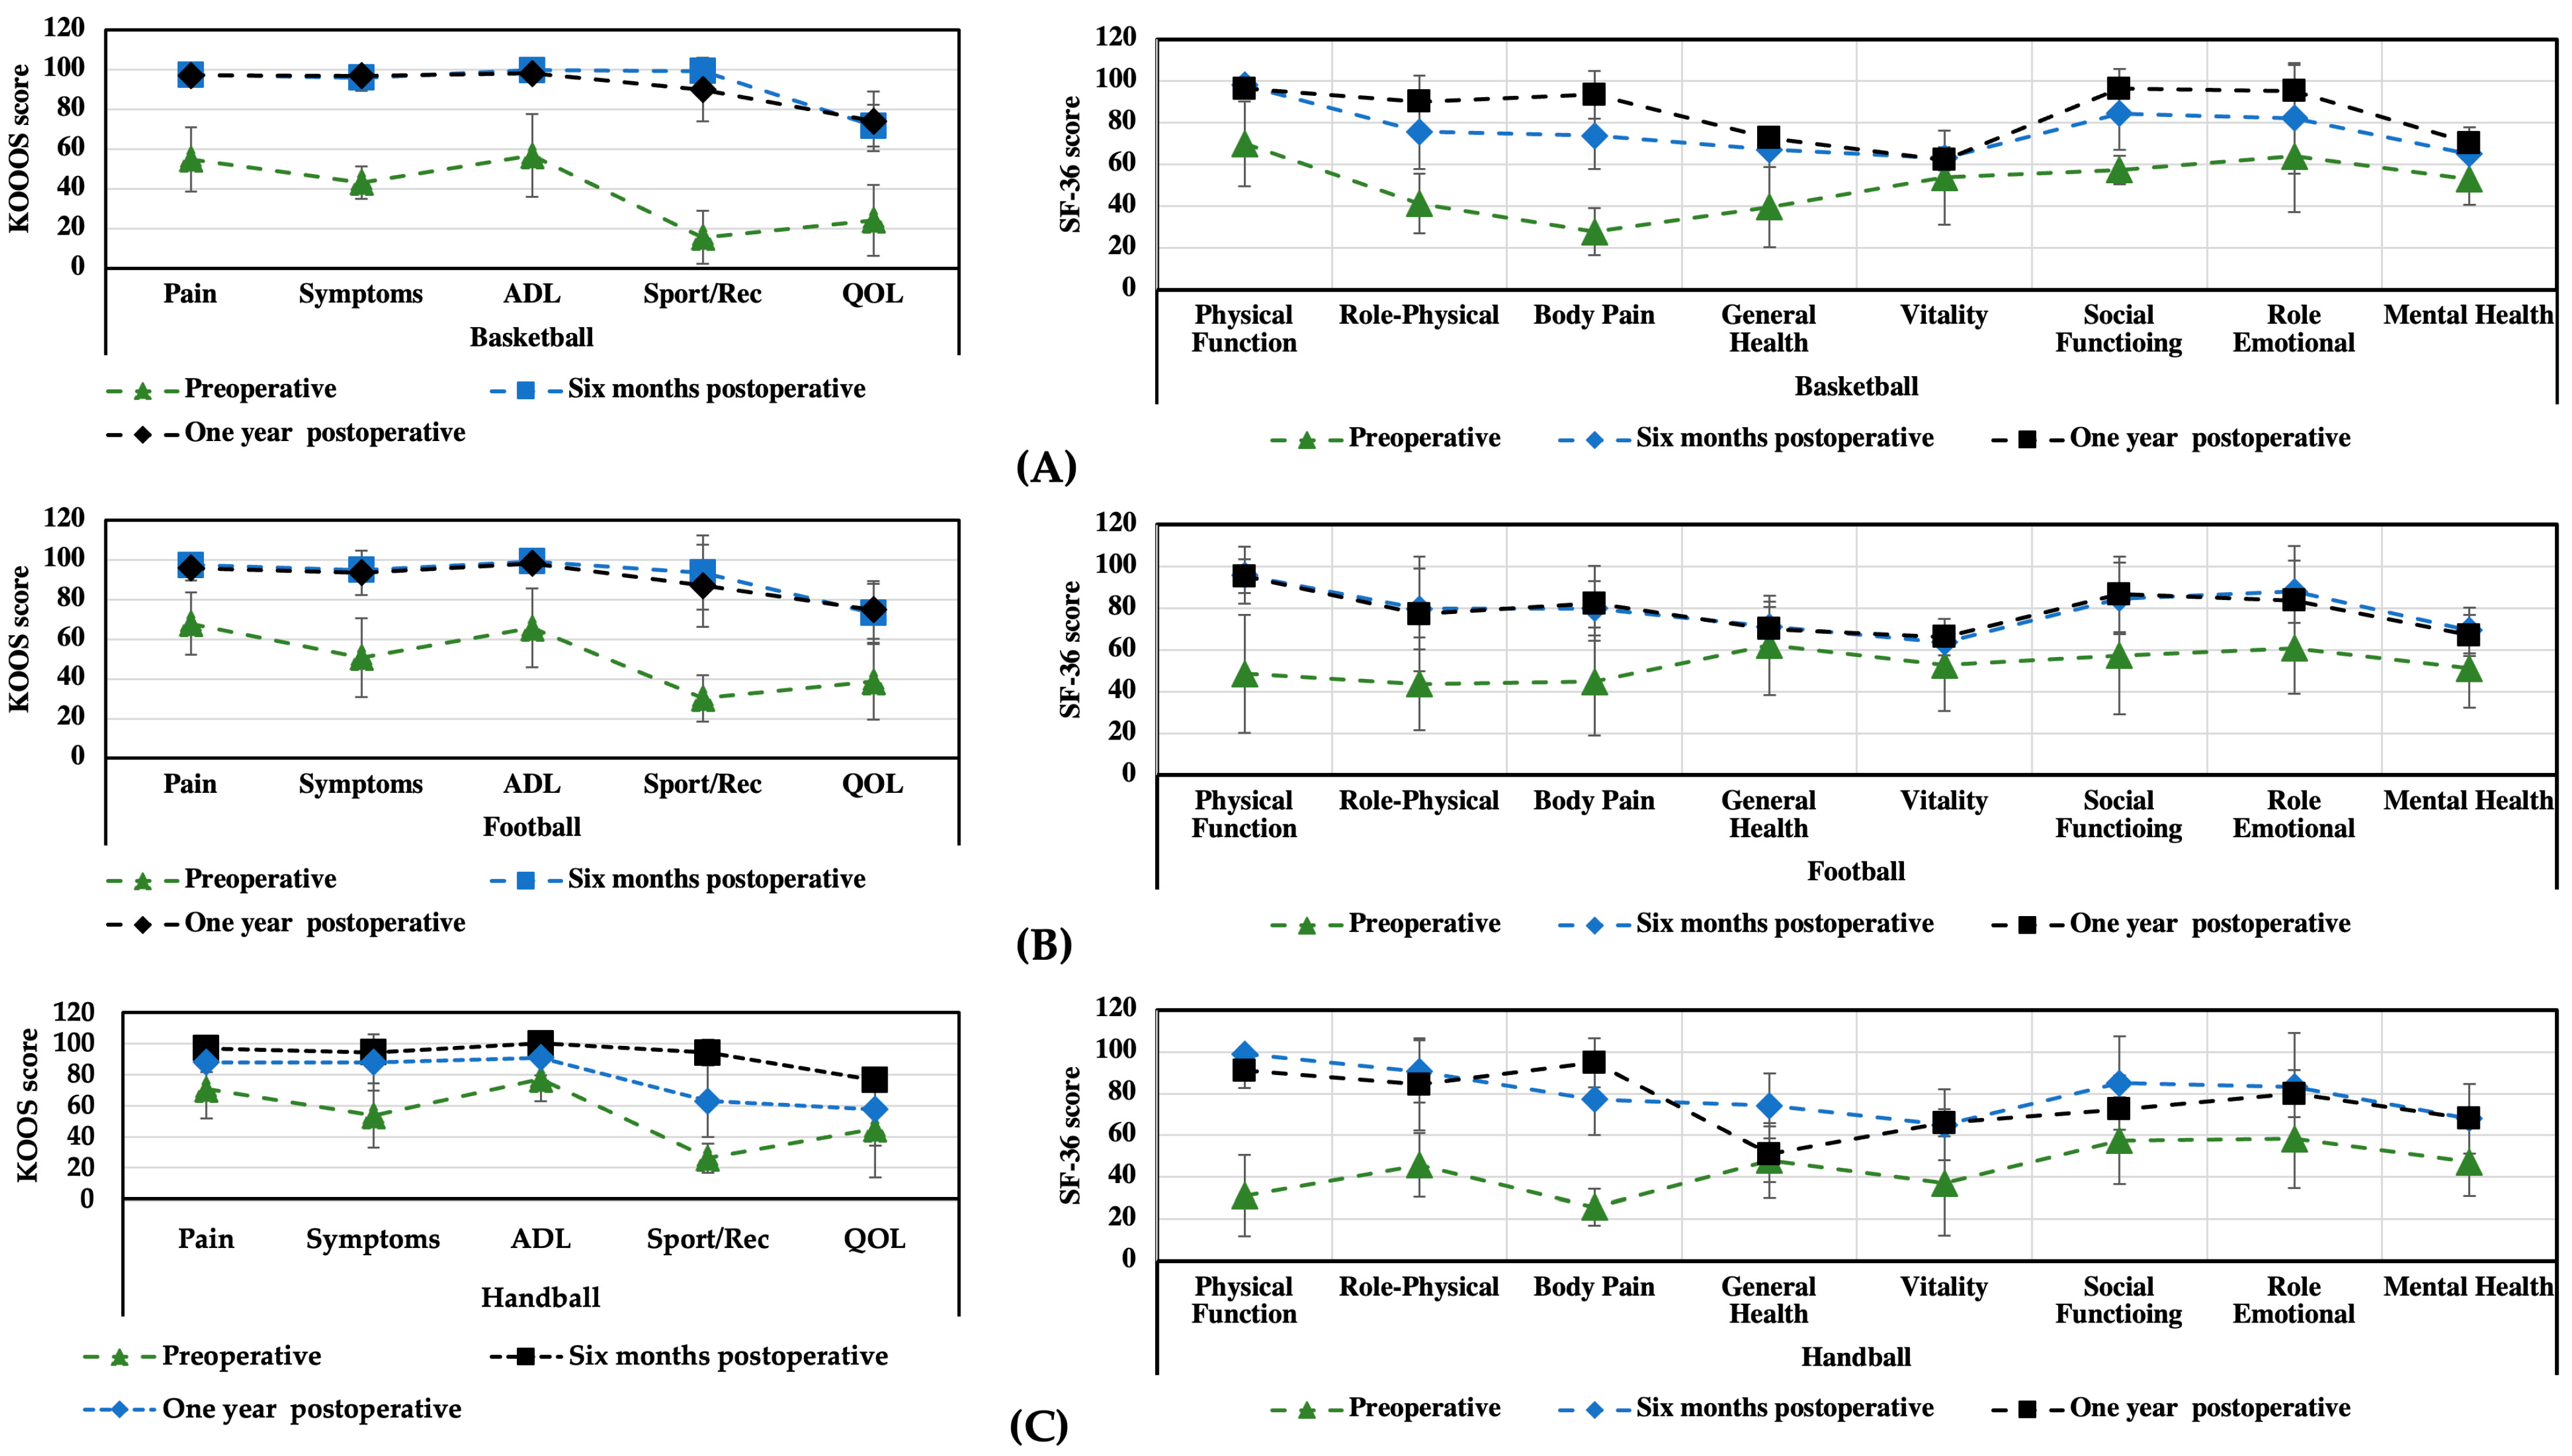

3.1. KOOS and SF-36 Scales